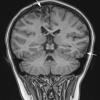

HSV-I Encephalitis (3)